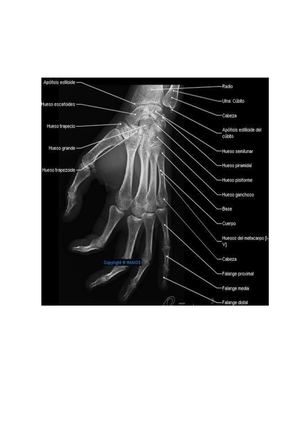

Anatomia Radiologica

En este libro usted podrá ver algunos términos de tipo médicos y de paso conoce las posiciones anatómicas, entre otras.